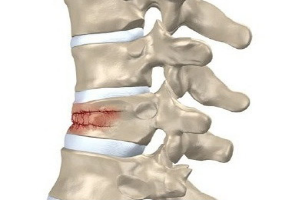

Позвонки грудного отдела: компрессионный перелом и лечение

Причиной сильной боли в спине может стать перелом грудных позвонков. Эта травма диагностируется довольно редко, в отличие от травм костей в других частях тела. Это связано с тем, что позвонки при отсутствии различных заболеваний обладают большой выносливостью и легко ломаются. Причины переломов Частая причина переломов — разного рода травмы. К ним относятся: Падение с большой …